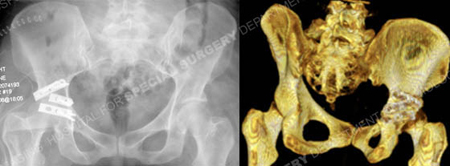

Postoperative anteroposterior and 3D CT reconstruction image revealing an acceptable reduction and placement of hardware.